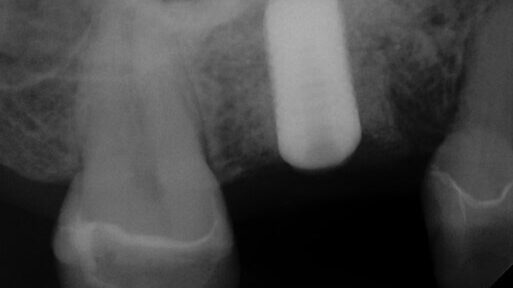

The patient presented on referral for retrieval of a fractured abutment and abutment screw from a BlueSkyBio MaxNP implant 4.3 in the #30 site.